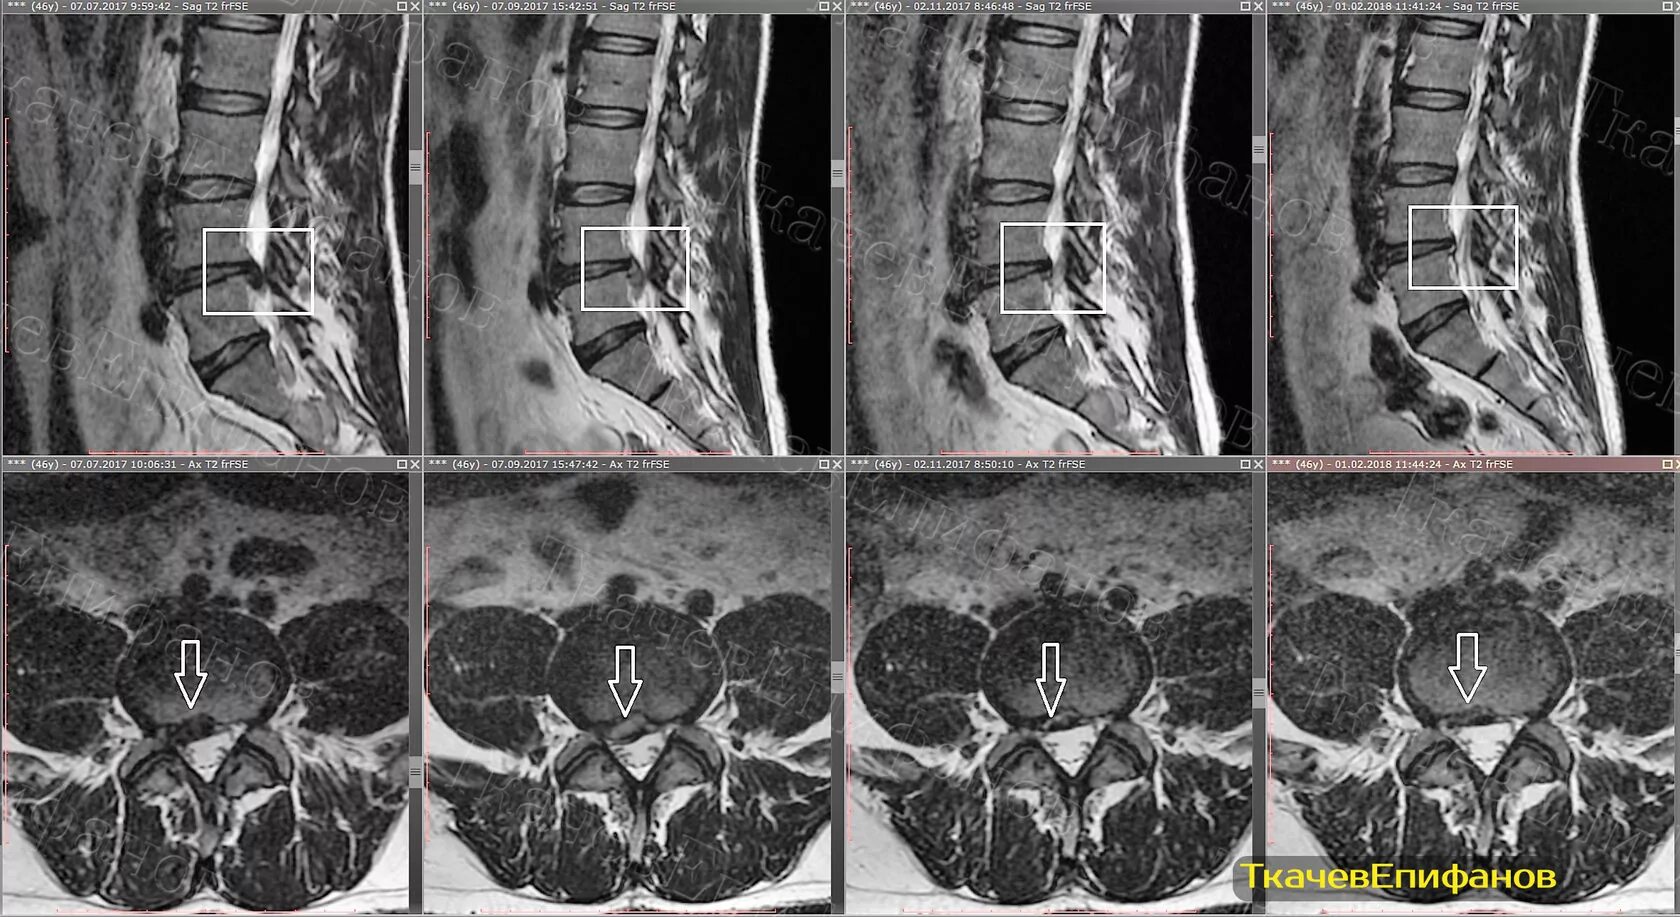

Чем отличается кт от мрт поясничного отдела